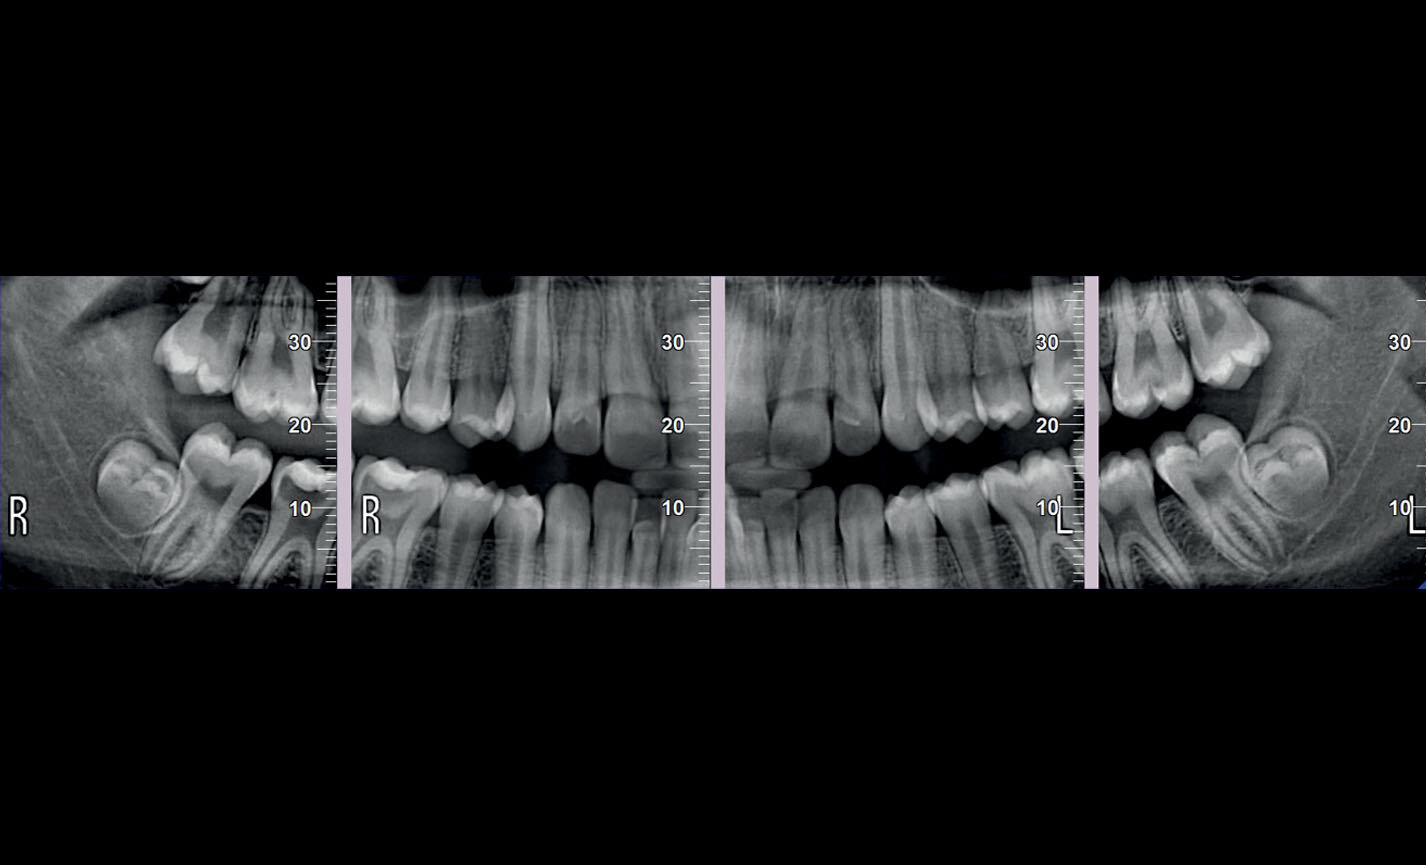

Orthopanoramiques

Projections bitewing, investigation limitée aux couronnes : haute résolution et faible dose, une alternative valable aux images intra-orales en cas de patients avec un fort réflexe de rejet.